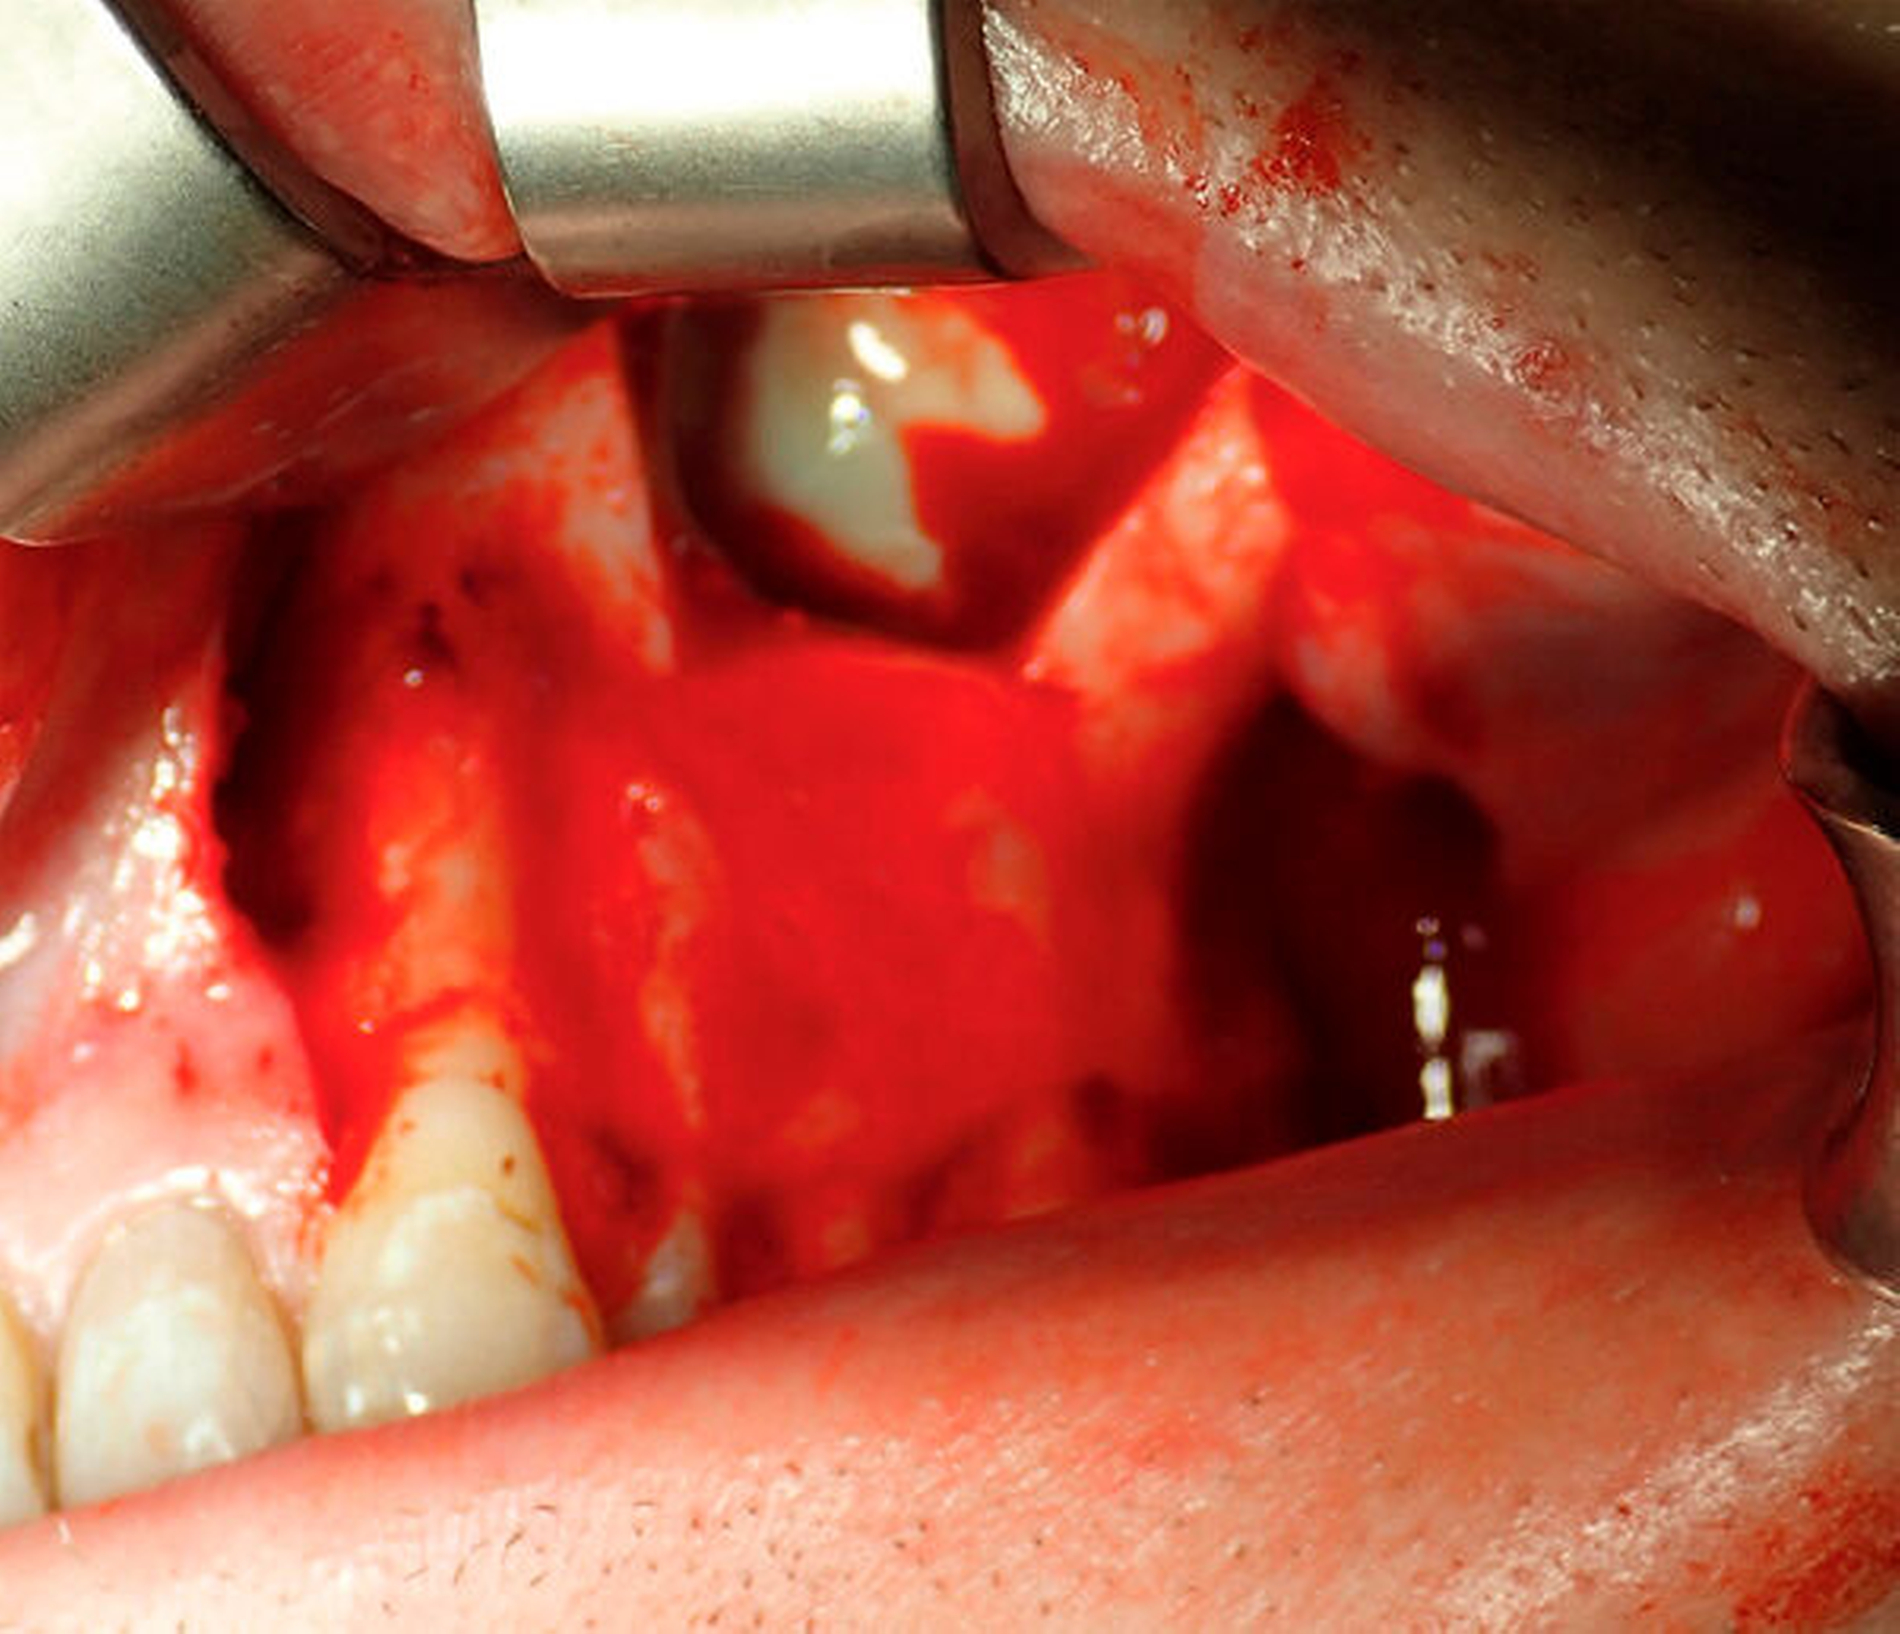

Nach ausführlicher Aufklärung und Einverständniserklärung durch den Patienten wurde eine transorale und transnasale, endoskopisch unterstützte operative Exploration der Kieferhöhle linksseitig mit Infundibulotomie (Teilentfernung des Proc. uncinatus und Eröffnung von Anteilen der vorderen Siebbeinzellen) in Intubationsnarkose im Rahmen eines zweitägigen stationären Aufenthalts durchgeführt. Transoral wurde die Kieferhöhle mithilfe eines osteoplastischen Zugangs nach der von Lindorf beschriebenen Technik eröffnet [Lindorf, 1984]. Schon bei Präparation des Knochendeckels entleerte sich reichlich Pus (Abbildung 3). Die Kieferhöhle war nahezu vollständig mit hyperplastischer Schleimhaut, putridem Exsudat und Schleimresten ausgefüllt (Abbildung 4). Es zeigte sich eine nicht knöchern konsolidierte Alveole regio 28, die mit Granulationsgewebe und Narbenzügen ausgekleidet war. Durch die stark angeschwollenen, entzündlichen Schleimhautareale war der natürliche Abfluss über das Ostium naturale nicht mehr gegeben (Abbildung 5).